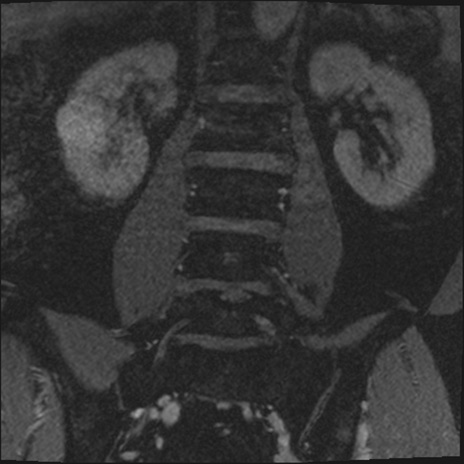

【整形】TIPS症例2 腰椎MRI 3D(冠状断像)

【症例】70歳代男性

【主訴】左下肢痛

【現病歴】2週間前くらいから腰痛、左下肢痛あり。左臀部から大腿、下腿外側のしびれが常時ある。歩行とともに同部位の痛みあり。

【身体所見】Lasegue70-/60+、Bragard-/±、PTR ±/±、ATR -/-、IP 5/5、TA 5/4、TS 5/5、EHL 右第1足趾なし/3、FHL 5/5、hypersthesia(-)、足背動脈触知良好

異常所見と診断は?